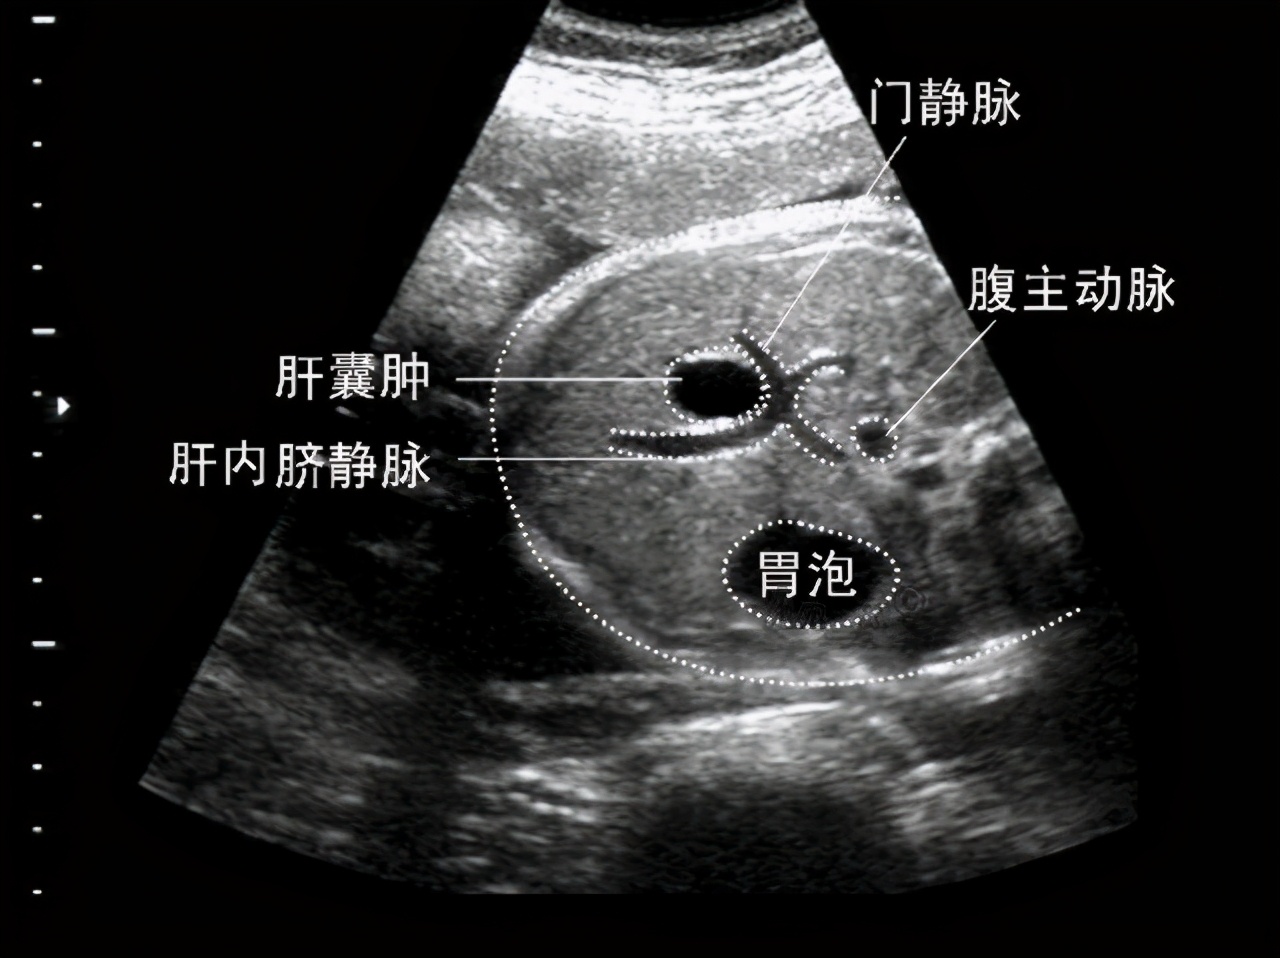

●经过多年的临床实践发现,其实超声是诊断肝囊肿最简便易行的方法, 可作为肝囊肿的诊断依据, 确诊率超过95%。它已有效应用于肝囊肿的筛查, 甚至还可用于胎儿先天性肝囊肿的诊断。有大量的临床实验表明,典型的单纯性囊肿超声图像表现为内部为无回声或仅有少量低水平回声, 囊壁薄, 边缘光滑、整齐, 后壁回声增强。注意了,若囊肿合并感染或出血, 则囊内可出现弥漫性中、低水平回声, 有时底部可有分层现象, 囊壁也可增厚边缘不规则。

●虽说CT、磁共振等影像学检查方法也可显示肝囊肿的结构, 但相比之下, 其实还是超声来得更简单方便、费用低, 也容易被老百姓接受。此外, 超声对肝囊肿的敏感性也很高, 可显示肝内小至2 mm的囊肿,超声还可在对肝囊肿进行定性评价的基础上, 精确地估算囊肿的大小、形态及位置等, 从而对囊肿进行分级,故而这就是我推荐B超检查的理由。